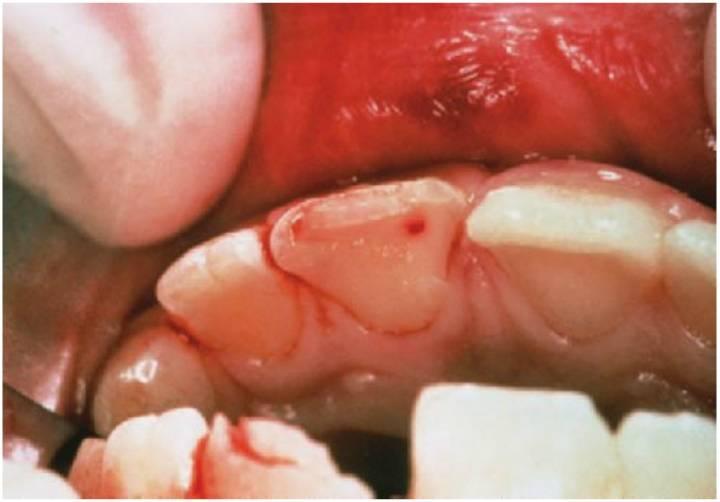

Fracturas coronorradiculares

Para poder llevar a cabo una evaluación completa de la extensión de la fractura deben extraerse siempre los fragmentos coronales (fig. 7.25).